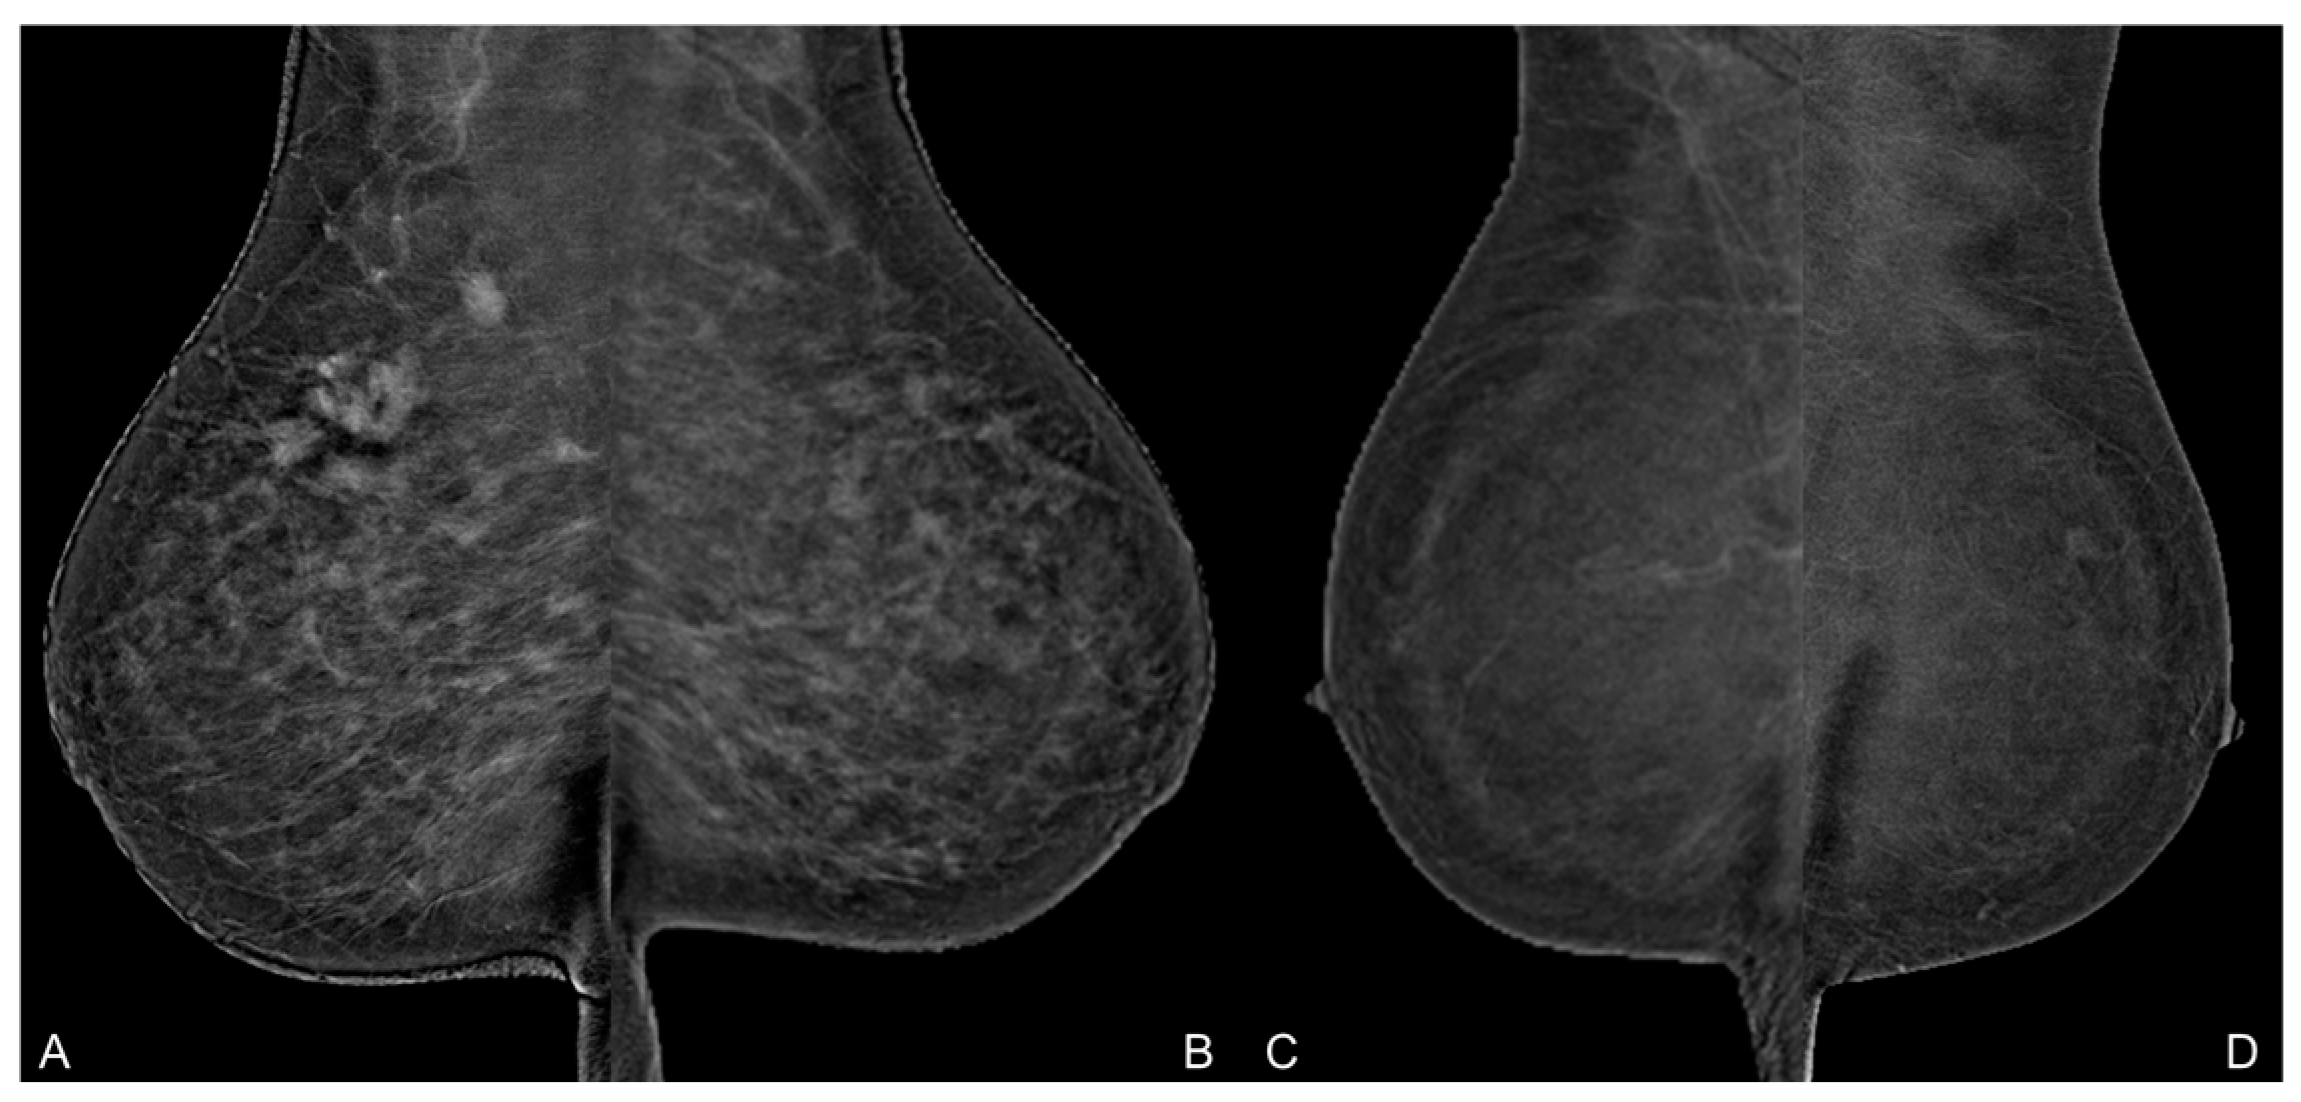

- Meucci, R.; Pistolese, C.A.; Perretta, T.; Vanni, G.; Beninati, E.; Di Tosto, F.; Serio, M.L.; Caliandro, A.; Materazzo, M.; Pellicciaro, M.; et al. Background Parenchymal Enhancement in Contrast-enhanced Spectral Mammography: A Retrospective Analysis and a Pictorial Review of Clinical Cases. In Vivo 2022, 36, 853–858. [Google Scholar] [CrossRef]